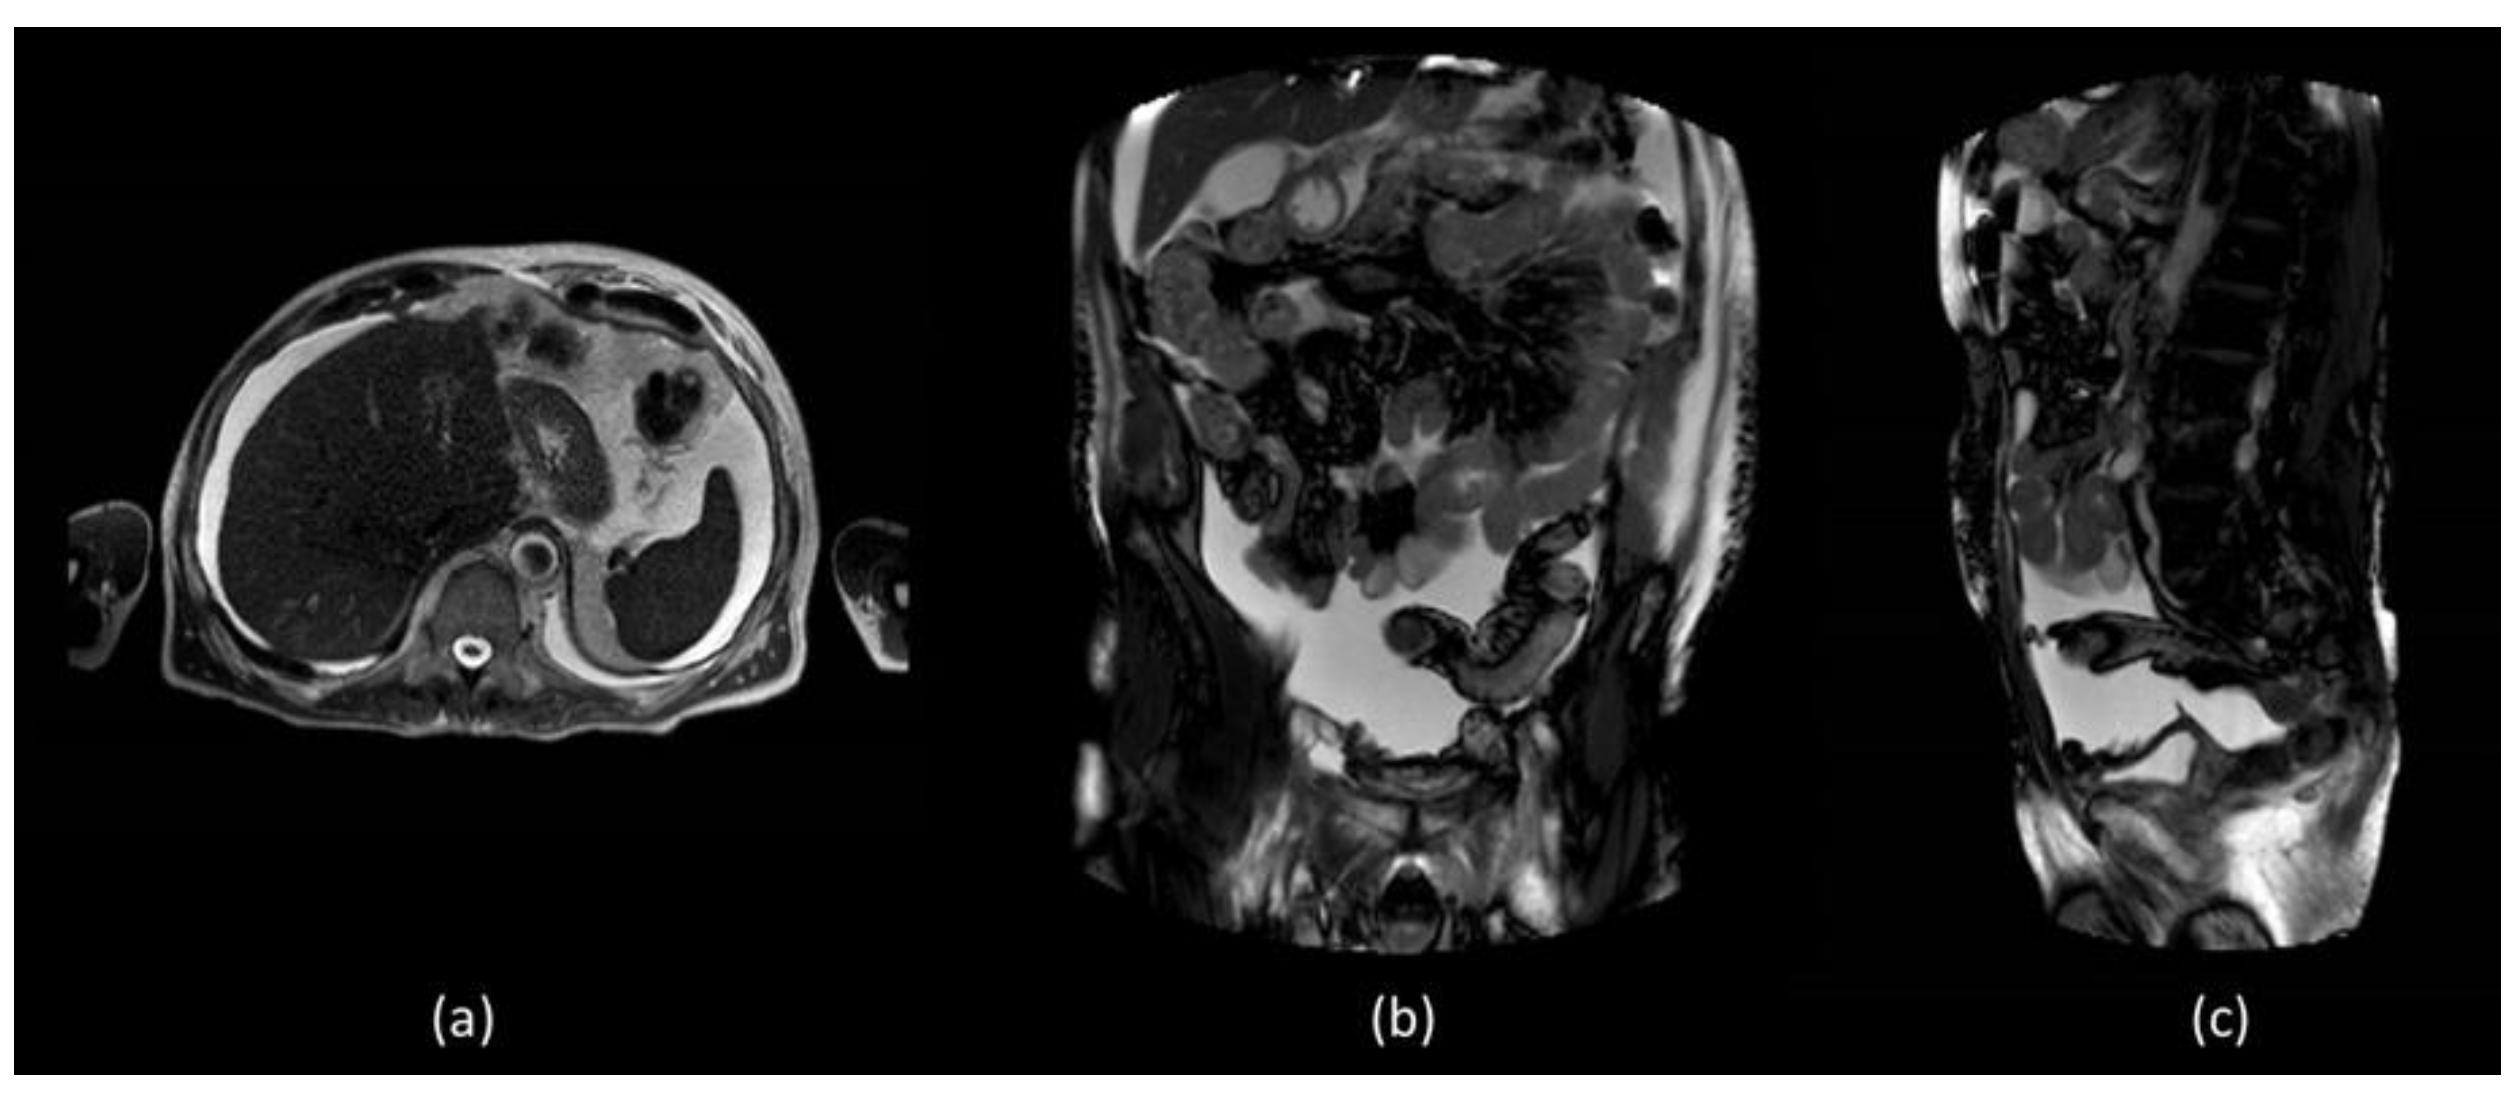

In order to better assess the post-surgery pelvic region, abdominal MR was performed which did not show evidence of surgical injuries and liver diseases (Figure 2).

Figure 2.

MR T1 weighted (a) axial section of the liver did not show diseases but confirmed the presence of massive fluid effusion, visible in the supra and submesocholic space and also in the coronal (b) and sagittal images (c).